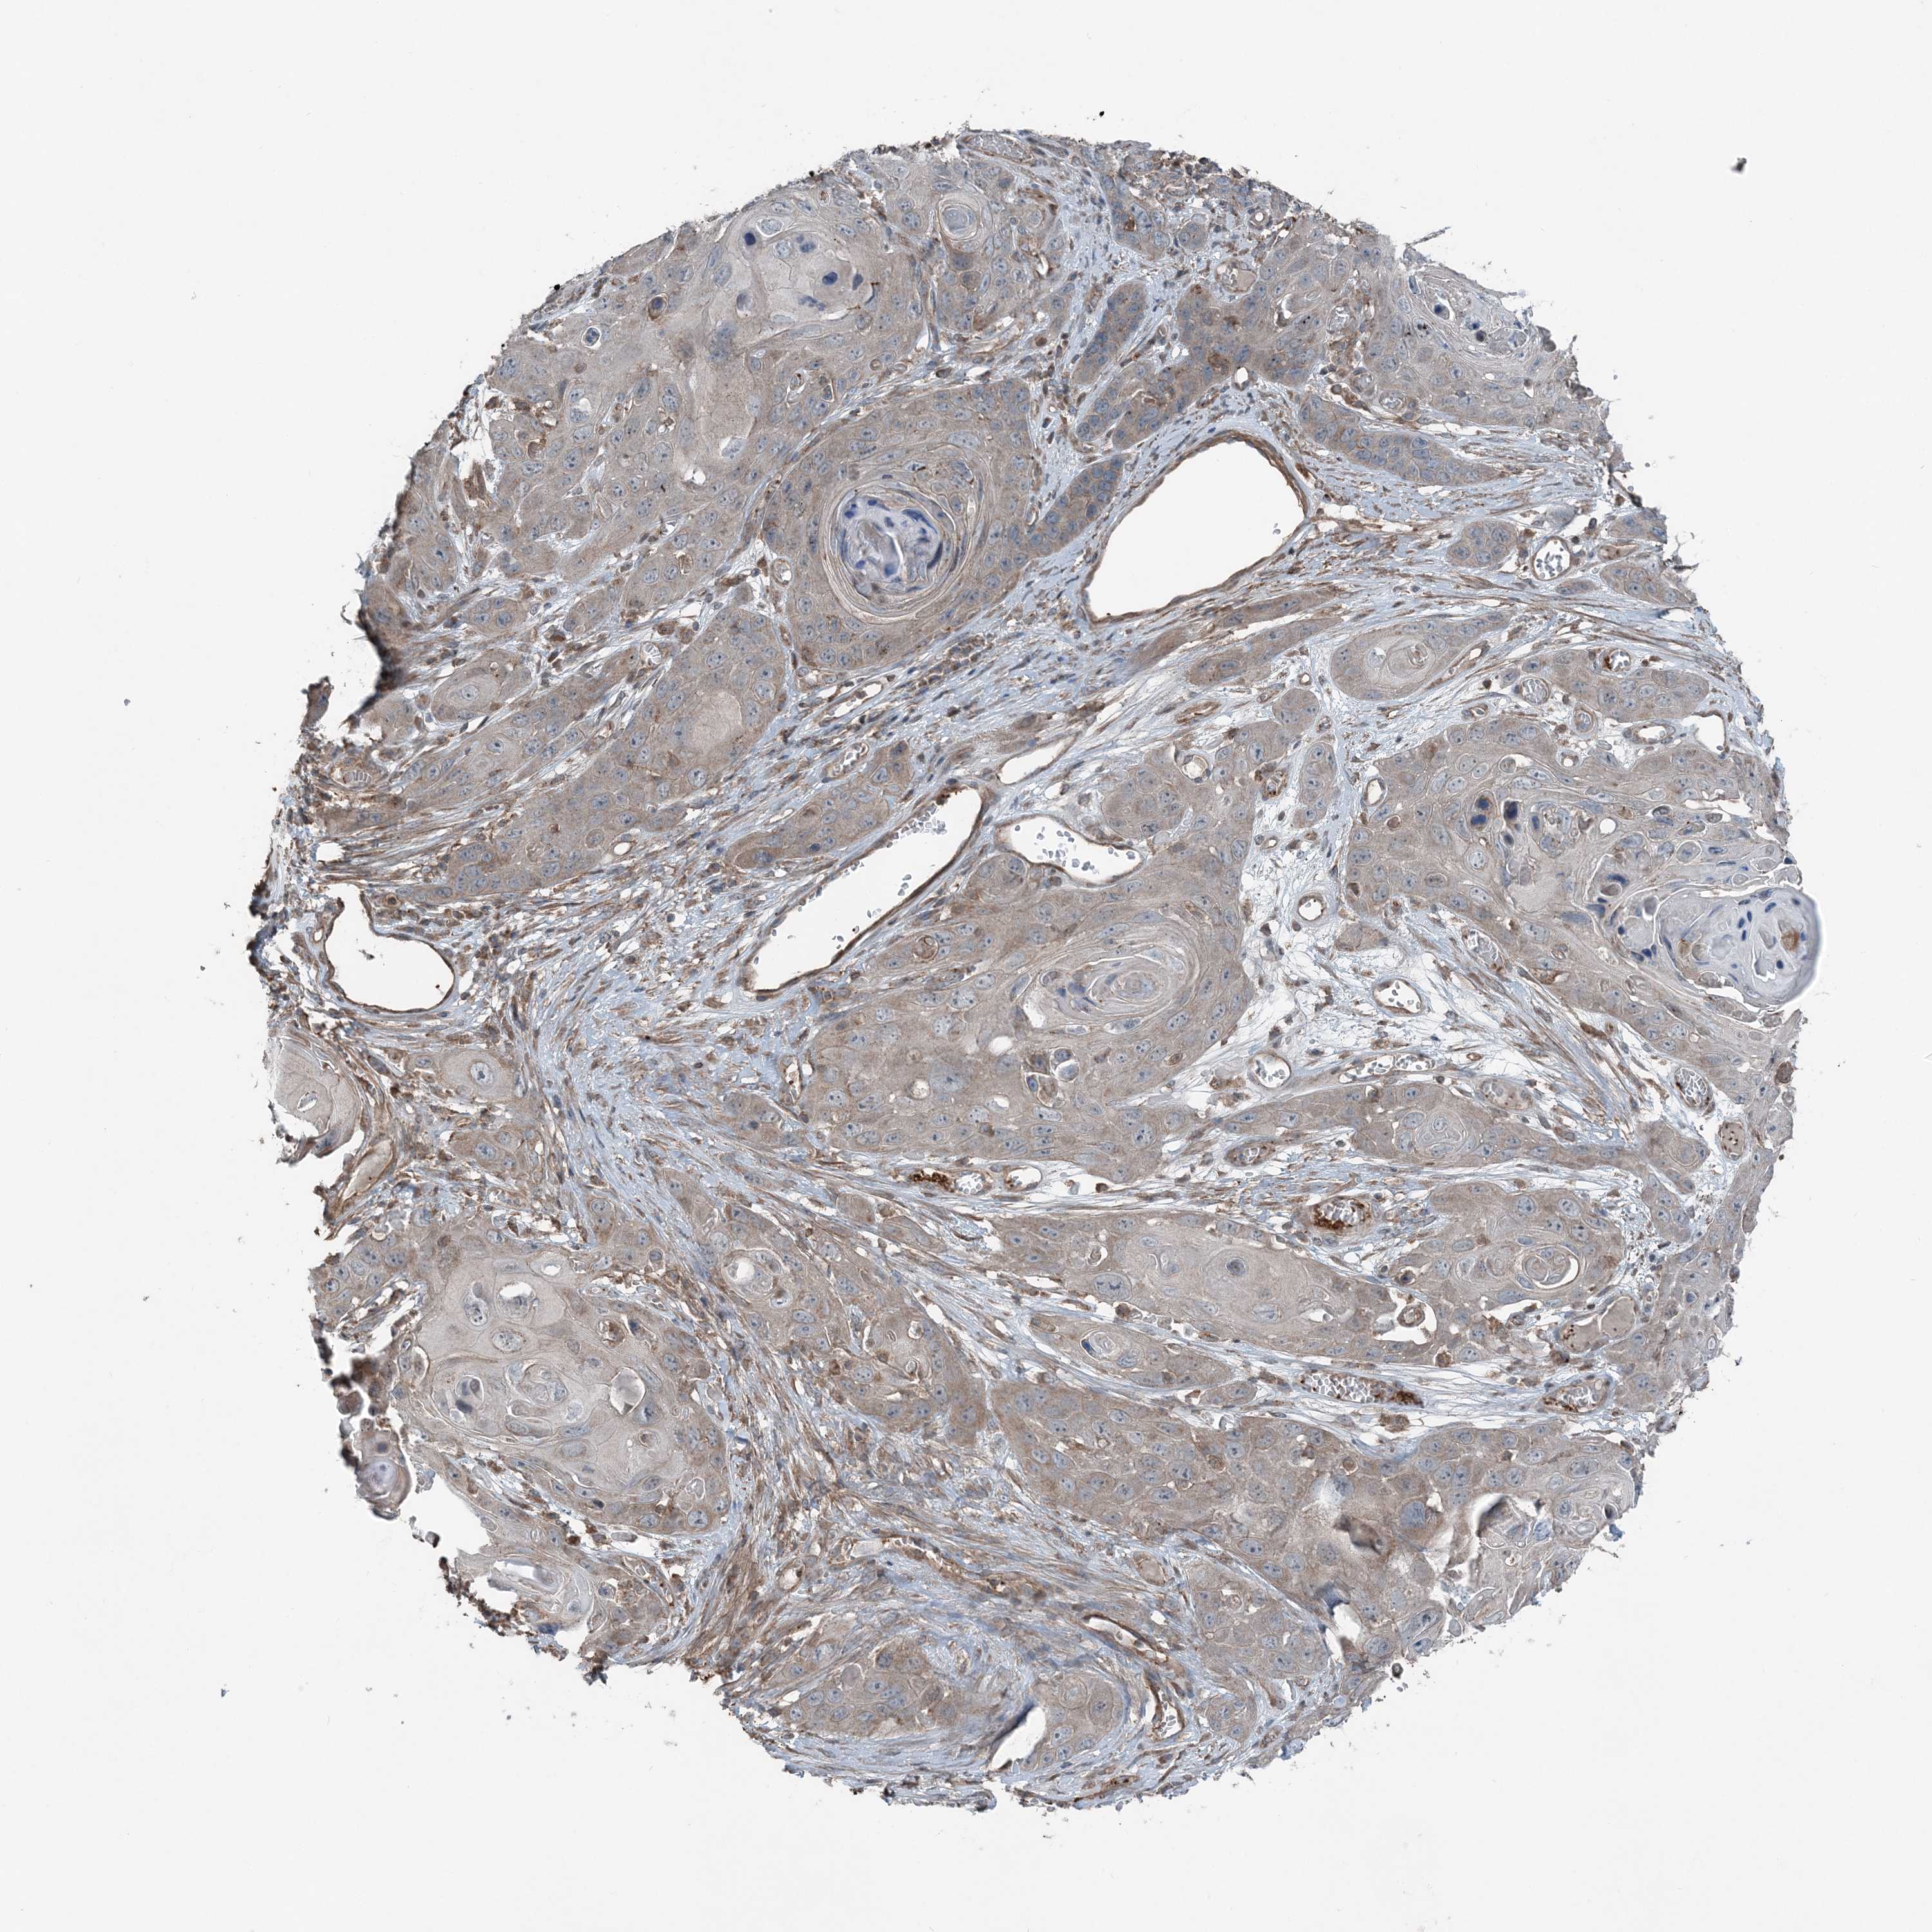

SKIN CANCER - Protein expressioni

A mouse-over function shows sample information and annotation data. Click on an image to view it in a full screen mode. Samples can be filtered based on level of antibody staining by selecting one or several of the following categories: high, medium, low and not detected. The assay and annotation is described here.

Antibody stainingi

Antibody staining in the annotated cell types in the current human tissue is reported as not detected, low, medium, or high, based on conventional immunohistochemistry profiling in selected tissues. This score is based on the combination of the staining intensity and fraction of stained cells.

Each image is clickable and will lead to virtual microscopy that enables deeper exploration of all samples and also displays staining intensity scores, fraction scores and subcellular localization as well as patient and tissue information for each sample.

Antibody HPA036668

Squamous cell carcinoma, NOS